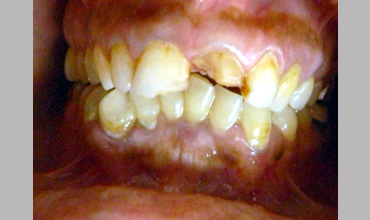

Management Of Fractured Central Incisor With Biological Post